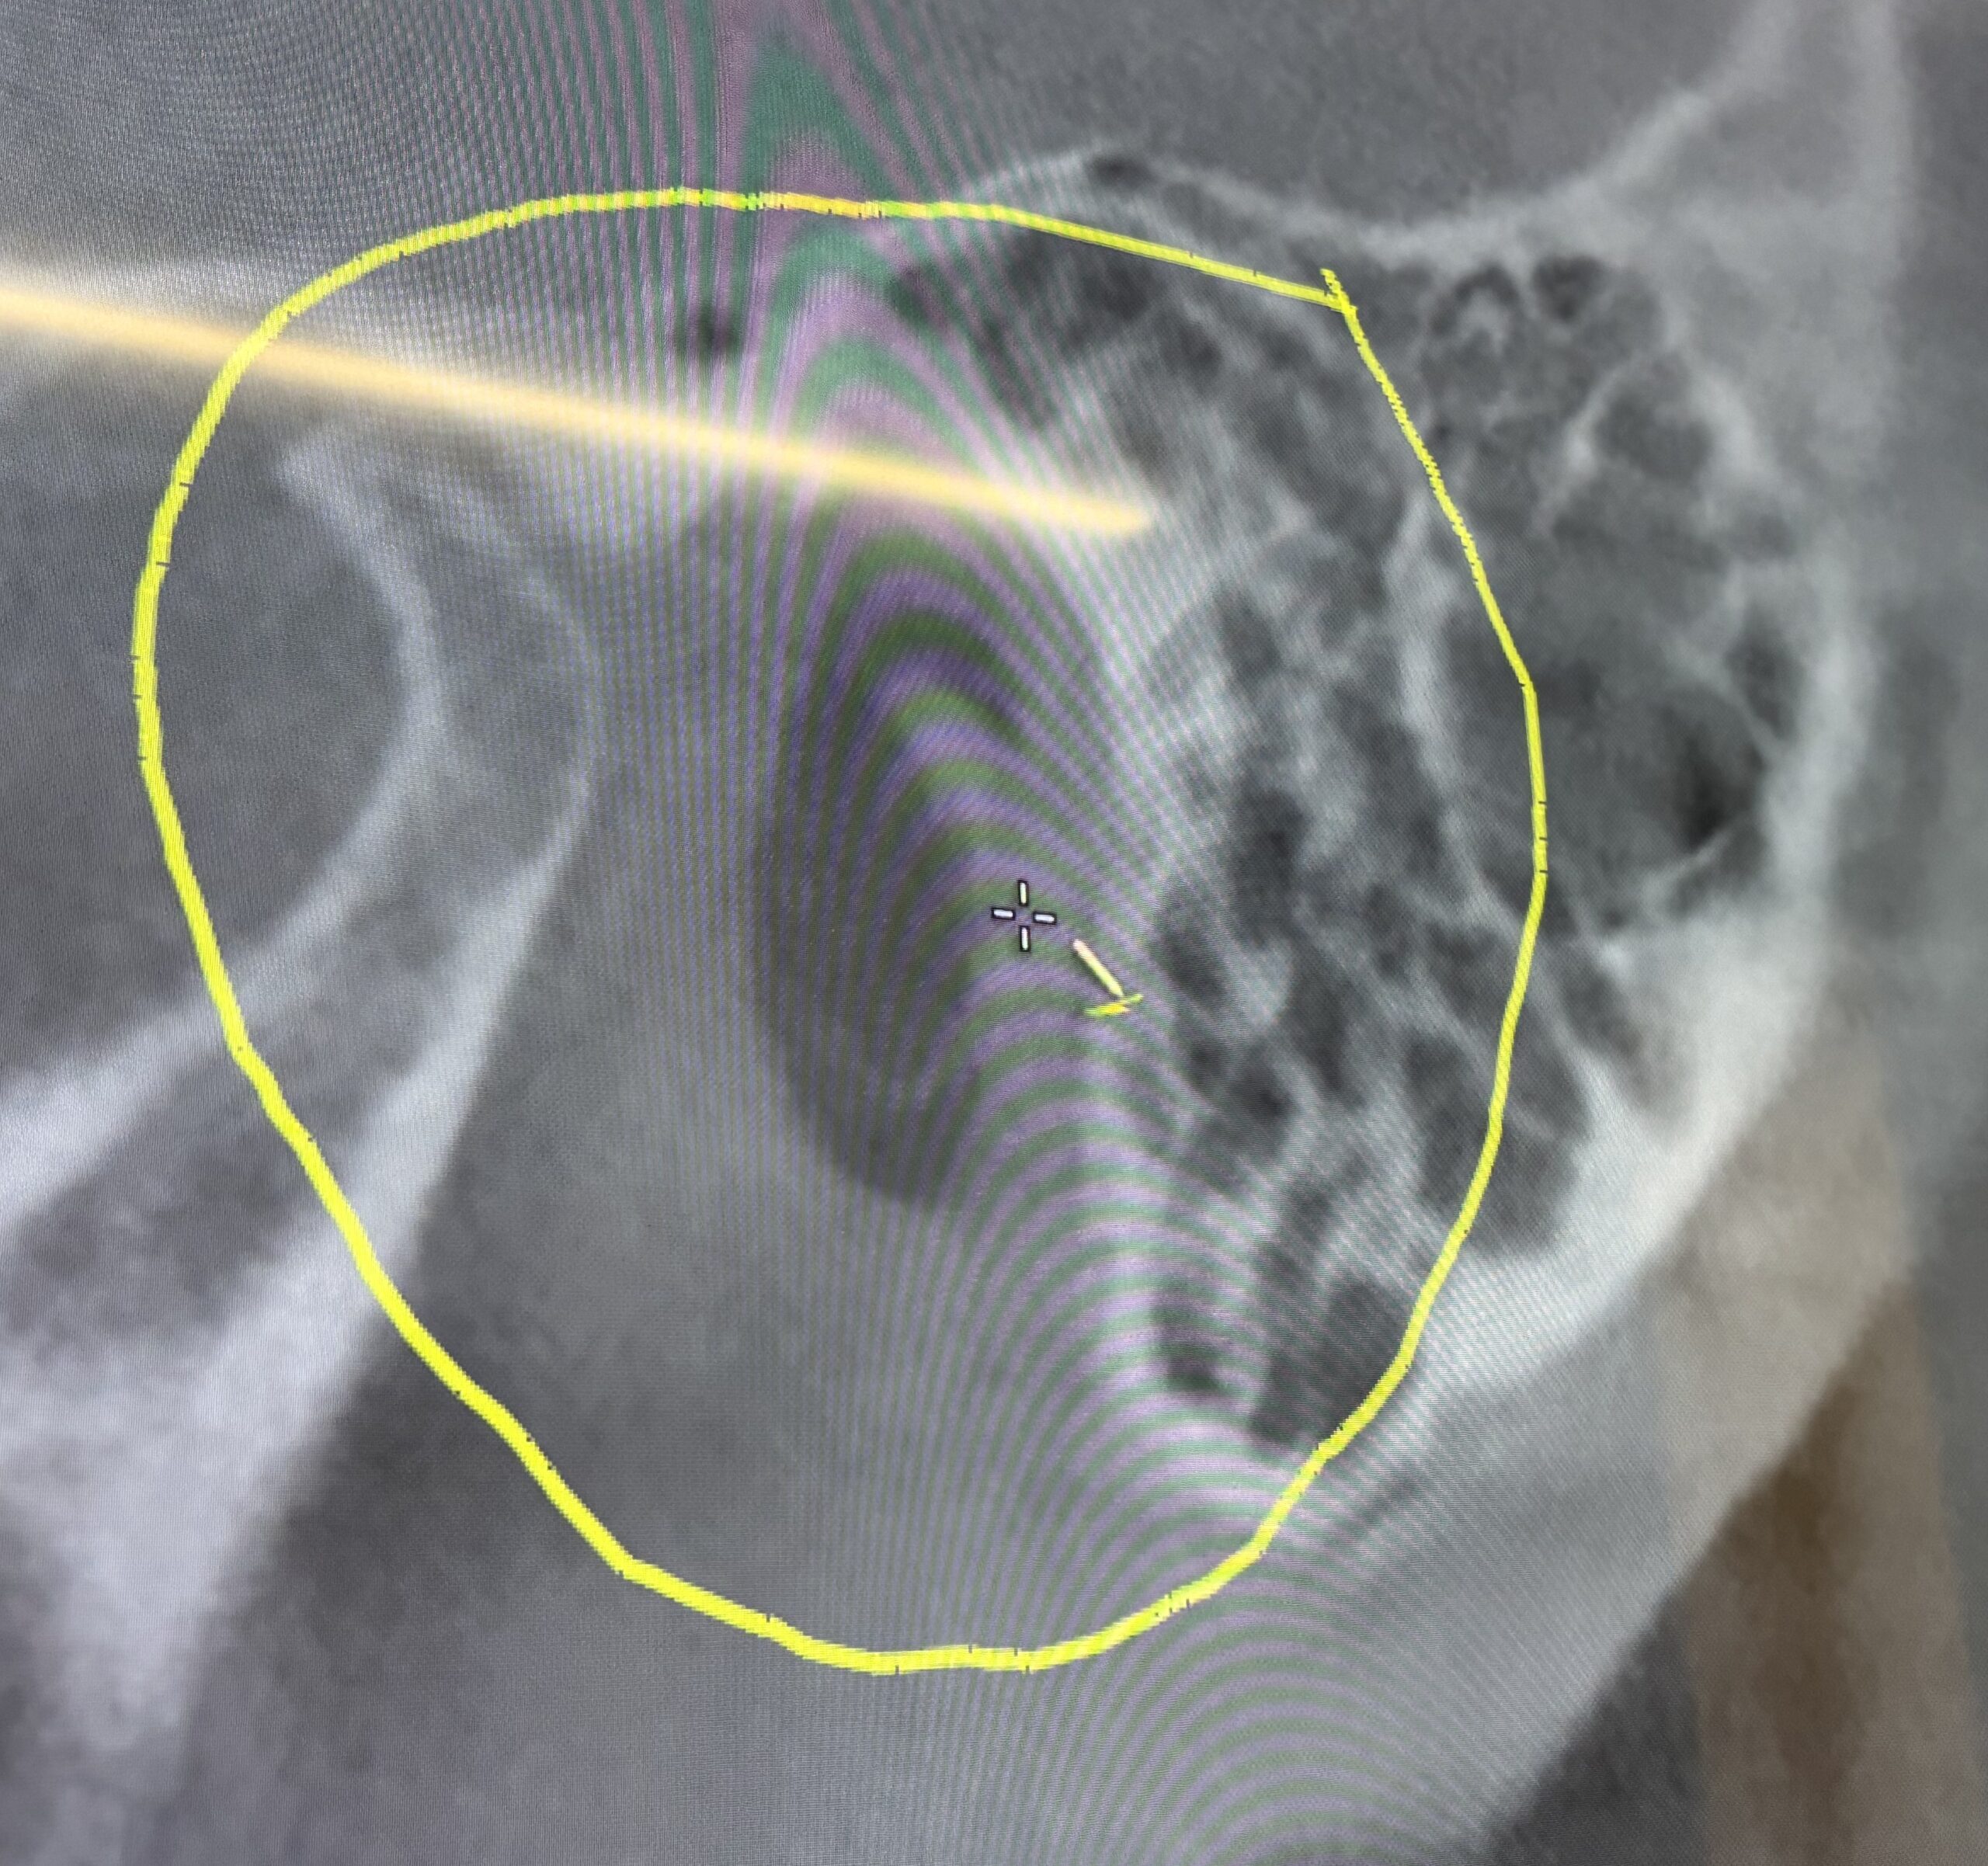

Ten days later I’m sitting with my Phoenix dentist relating my Raphe story as he pulls up my recent April scan.  Unfortunately, a CBCT scan is not the appropriate scan to study Raphe. For whatever reason, I asked him to look in the Eustachian tube area based on back-and-forth conversations with my Santa Cruz osteopath about this area as a potential source of my symptoms. This unplanned conversation produced a large surprise.

Zooming into this area, the dentist exclaimed,

Look at this!”.

The big-screen TV displaying the CBCT scan is

definitely ‘in-your-face’. It was very easy to see what the dentist was referring to in my Eustachian tube as he manipulated the scan forwards and backwards.

“What is it?” I exclaimed as I peered at the ‘thing’

that was hanging into an opening.

“Looks like a calcification,” was his shocking statement.

After twenty-nine years of saying there was something in the tissue,  I was so stunned  that I couldn’t even continue a conversation with him before he left for his next patient.